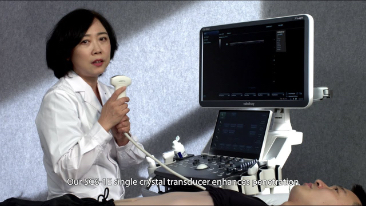

Mindray Resona General Imaging solutions help clinicians realize more accurate and efficient diagnosis and treatment results through comprehensive subdivision application probes and efficient clinical application tools.

General Imaging Products